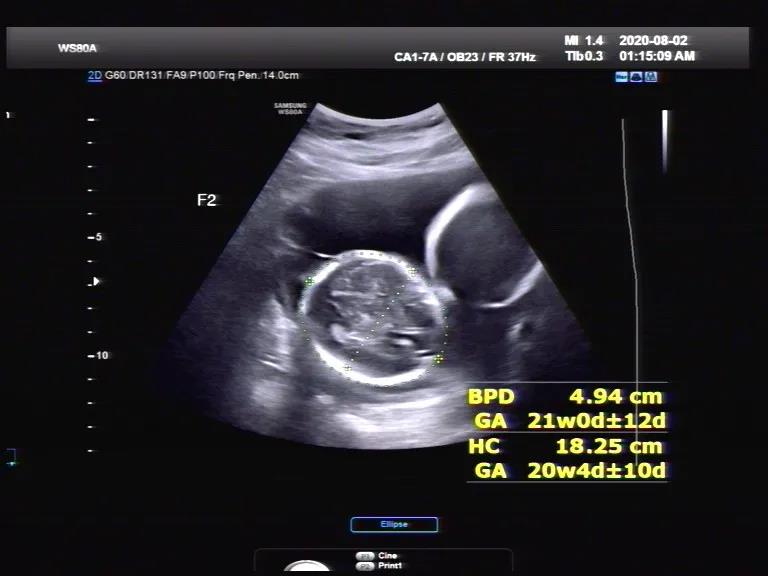

判斷絨毛膜性最好的孕周是7-13周,錯過這個時間,想要清楚的判斷絨毛膜性,就非常難了。胎兒門診的醫(yī)生與超聲醫(yī)生一起,結(jié)合超聲表現(xiàn),認為王女士單絨毛膜雙羊膜囊可能性大。

在醫(yī)生的細心指導(dǎo)下,在王女士孕32周時,超聲提示兩個寶寶的體重差已經(jīng)達到30%,不過多普勒血流正常,考慮選擇性生長受限I型。胎兒門診的醫(yī)生聯(lián)合產(chǎn)科專家、超聲專家、NICU專家,一起組織了多學(xué)科會診,制定產(chǎn)前產(chǎn)后一體化管理計劃。專家一致達成共識:考慮到不可預(yù)測的死胎風(fēng)險,建議入院,進行促胎肺成熟治療,密切監(jiān)測胎兒宮內(nèi)情況,在條件允許下盡量延長孕周。